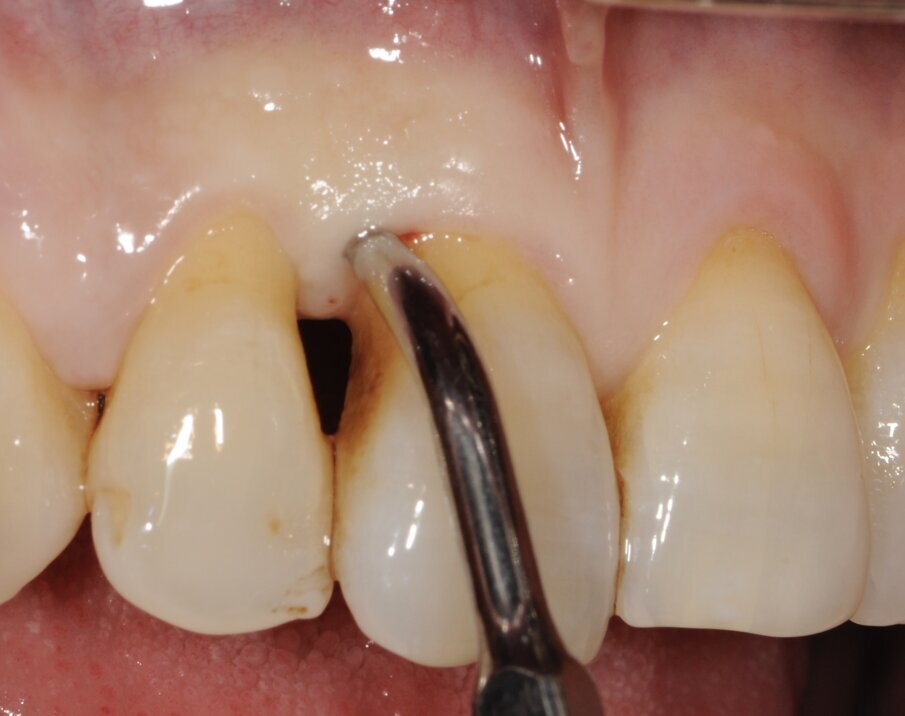

Un paziente di 56 anni non fumatore viene riferito alla nostra osservazione per il trattamento della parodontite. Dopo aver effettuato la diagnosi (parodontite generalizzata Stadio III, Grado C) il paziente è sottoposto a due sedute di scaling sopra gengivale (step 1) e successivamente a 4 sedute di debridement sotto gengivale effettuato con strumenti ultrasonici e manuali (step 2). Al momento della rivalutazione si registra un miglioramento degli indici di placca e di sanguinamento (FMPS e FMBS ≤ 20%) e una riduzione di tutte le tasche parodontali (PD<4 mm) in ciascun sestante a eccezione del secondo sestante. In questa regione si registra una tasca residua con PD = 6 mm a carico dell’elemento 1.1, associata a un riassorbimento osseo radiografico prevalentemente orizzontale (Figg. 1, 2). Considerando il miglioramento di tutti i parametri e degli indici parodontali e la presenza di una tasca con PD = 6 mm a carico di un solo elemento dentario si decide di ritrattare l’elemento 1.1 con terapia non chirurgica (step 3). La nuova ristrumentazione è stata effettuata seguendo il protocollo Clean&Seal che prevede l’associazione di ipoclorito di sodio stabilizzato con amminoacidi e acido ialuronico reticolato ad alto peso molecolare in combinazione con il debridement sotto gengivale. Dopo anestesia locale, è stato applicato all’interno della tasca l’ipoclorito di sodio stabilizzato con amminoacidi e lasciato agire per circa 60 secondi (Fig. 3). Successivamente è stata effettuata la strumentazione sotto gengivale mediante l’utilizzo di strumenti ultrasonici e manuali (Figg. 4, 5). Alla fine della procedura di strumentazione, nella tasca è stata effettuata un’irrigazione con soluzione salina sterile e la procedura di applicazione di ipoclorito di sodio e di strumentazione meccanica è stata ripetuta per 4 volte. Un fattore critico per garantire un risultato migliore è di evitare di instillare qualsiasi soluzione a base di clorexidina nella tasca, in quanto inibisce l’adesione cellulare. Alla fine del trattamento meccanico è stato inserito l’acido ialuronico reticolato ad alto peso molecolare all’interno della tasca per stabilizzare il coagulo e accelerare la guarigione (Fig. 6). Il controllo clinico è stato effettuato dopo 6 settimane dal trattamento con completa chiusura della tasca (Fig. 7).